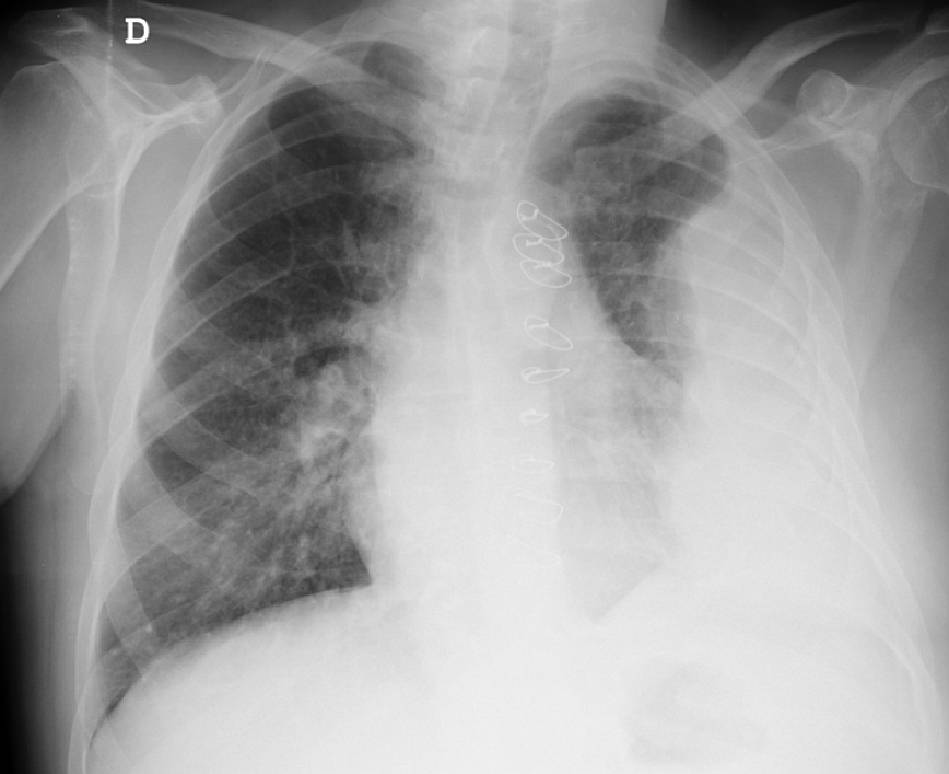

77-year-old male Caucasian patient was admitted with left-sided chest mass, first noticed 15 days before admission. At physical examination a non-tender tumefaction on the mid-axillary line of left chest wall was perceived.

There was no fever, chills or cough. The patient had a clinical history of pulmonary tuberculosis 50 years before.

What’s the diagnosis ?